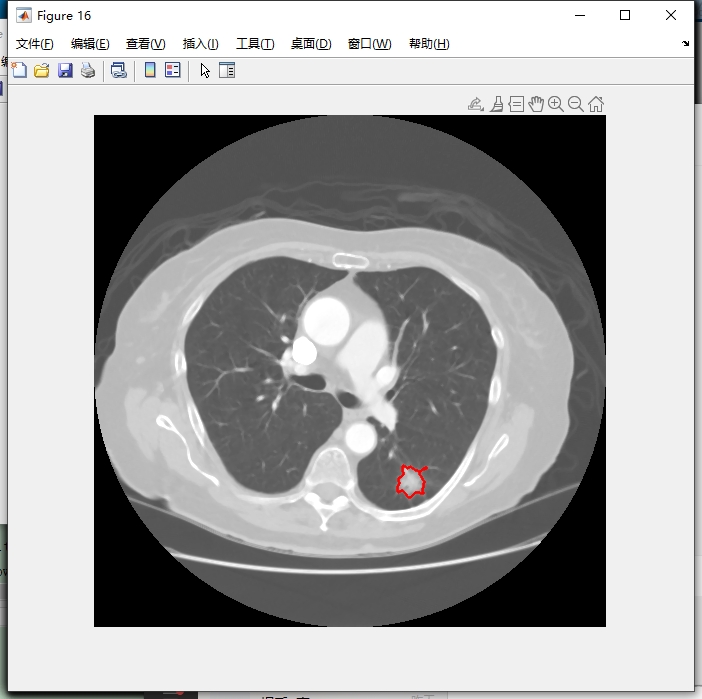

5. 可视化标注文件

读取医生的xml标注文件,可视化出医生的标注结果。

% 假设这里有个函数parse_xml来解析xml文件获取标注信息

[annotations] = parse_xml('your_xml_file.xml');

% 这里简单假设annotations包含标注位置等信息,在图像上绘制标注

for i = 1:size(annotations, 1)

% 根据标注信息获取坐标等,这里假设获取到x,y坐标和半径r

x = annotations(i, 1);

y = annotations(i, 2);

r = annotations(i, 3);

rectangle('Position', [x - r, y - r, 2 * r, 2 * r], 'EdgeColor','r');

end

代码分析:先调用假设的 parse_xml 函数解析xml文件获取标注信息存到 annotations 里。然后通过循环遍历每个标注,从 annotations 里获取坐标和半径等信息,使用 rectangle 函数在图像上绘制红色矩形来表示标注位置。